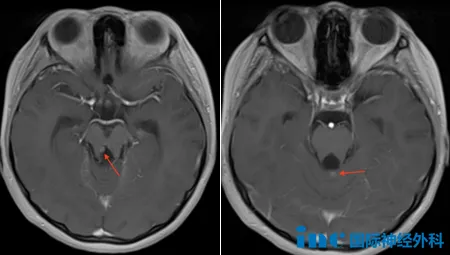

然而,事情似乎正在朝着坏的方向发展。半年后的一次复查,核磁上显示:小脑蚓部、右侧大脑脚异常强化灶大致相仿,双侧脑室室管膜下可见数个小结节,医生怀疑为肿瘤复发或转移。

忧的是Rutka教授也不排除肿瘤残余或扩散的可能,其中右脑室周围和小脑蚓部的肿瘤结节,可能是原发性后颅窝大肿瘤的残留;但是,如果双侧侧脑室结节确实存在,那么它们很可能是肿瘤转移的迹象。

喜的是目前这些小结节并不大,有些甚至在核磁上也看不清,因此,如果想要确定肿瘤真的发生了扩散,安格可以先进行脊髓MRI检查。而对于后续的治疗,教授也给出了具体的建议。